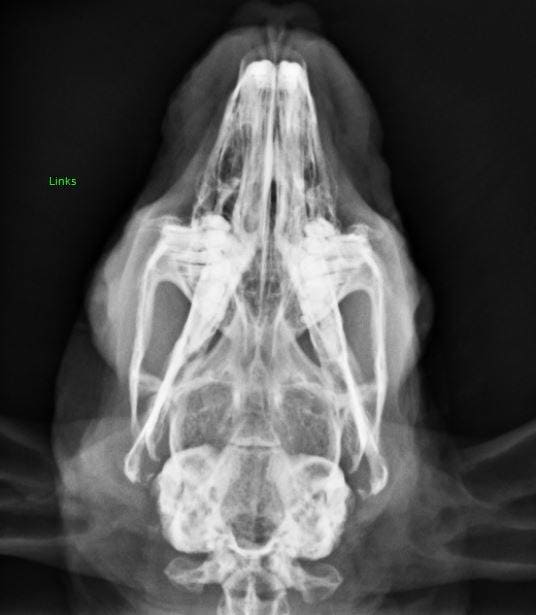

Short-headed dwarf rabbits (round head):

The short, rounded skull shape can lead to dental diseases and disorders of the nasolacrimal duct (watery or purulent eyes). More information on brachycephaly.

Short-headed rabbits are prone to breed-specific diseases.